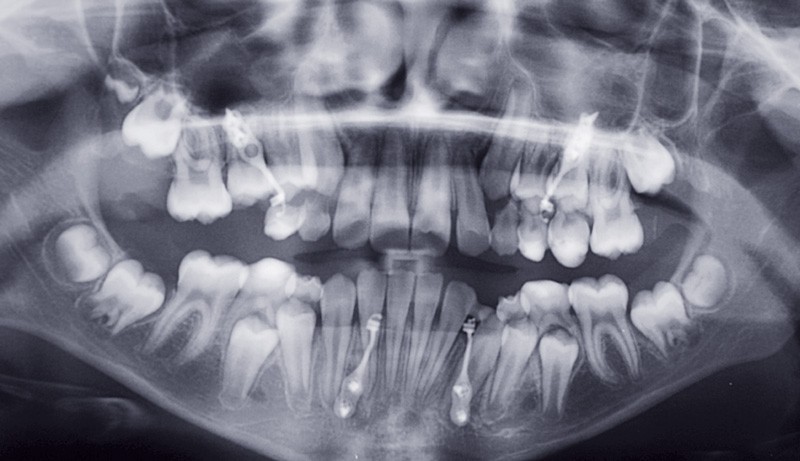

Cependant, la pose des plaques a été difficile du fait de la finesse du contrefort zygomatique et du peu de hauteur alvéolaire, en particulier au niveau du secteur I du fait de la rétention de la 16 (fig. 1).